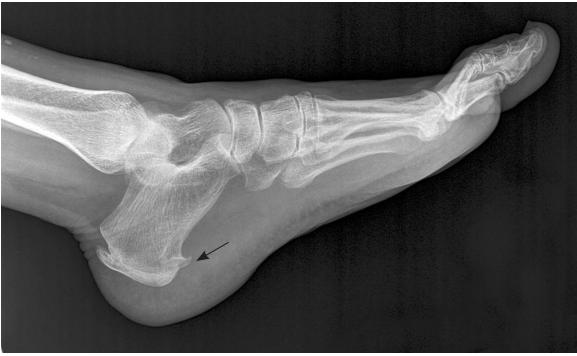

如果去医院拍片子,可能会发现如下图一般的跟骨骨刺(黑箭头所示)。

但是,一定关注:

并不是因为长骨刺,才得了足底筋膜炎。因为很多没有任何症状的人也会有这里的骨刺,而很多有足底筋膜炎的患者并没有跟骨骨刺。所以无论是疾病病因,还是后面的治疗,都跟这个骨刺没多大关系。哪些告诉你说能消骨刺治这个病的,别信就好。